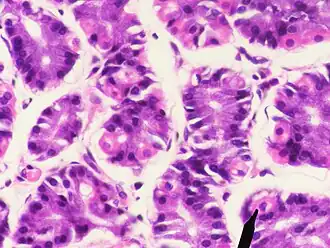

Microscopisch beeld van maagweefsel. Rechtsonder wordt een der pariëtale cellen aangewezen. | ||||

Pariëtale cellen zijn cellen die zich bevinden in de mucosa van de maag. Ze zorgen voor de productie van maagzuur, intrinsic factor (IF) en worden gestimuleerd door gastrine. Somatostatine is de belangrijkste inhibitor van de cel. Een goede functie van deze cellen is belangrijk voor de vertering en opname van voedsel en voor de bescherming van het lichaam tegen micro-organismen.

Onder in de pariëtale cel liggen blaasjes waarin een protonpomp zit, als de cel HCl moet produceren, gaan deze blaasje naar het afgiftekanaal toe en fuseren daar. Een belangrijke activator hiervan is histamine. Histamine grijpt aan op de H2receptor, die de second messenger cAMP (cyclisch adenosinemonofosfaat) vormt. cAMP stimuleert de fusie van de membraanblaasjes, acetylcholine en gastrine kunnen dit proces versterken door een verhoging van de calciumconcentratie in de cel.